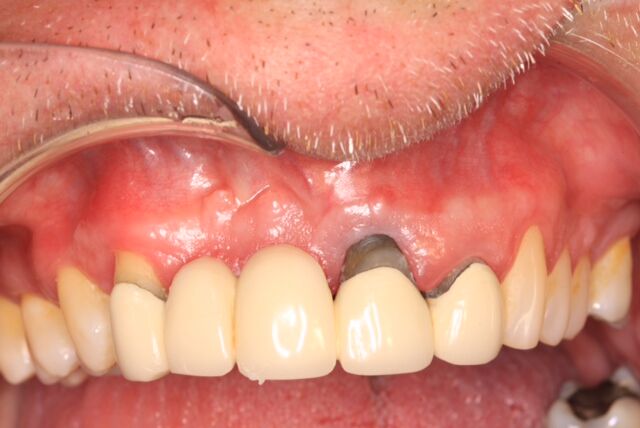

(10.) Initial clinical evaluation of Nos. 12 through 14 after crown on No. 12 and pontic on No. 13 removed.

Figure 10

A 67-year-old woman presented on an emergency basis with a bad odor and taste from crown No. 12, which had been diagnosed that day at hygiene recall as decayed and no longer attached to the underlying root (Figure 8 and Figure 9). The patient was anesthetized and the existing bridge was sectioned (Figure 10), leaving crown No. 14 intact. The No. 12 root was extracted and the site was fully debrided of granuloma. A platform shift implant was stabilized in excess of 45 Ncm in position No. 12, which was prosthetically correct. The soft tissue of pontic site No. 13 was contoured to mimic soft tissue contours of a bicuspid and an implant was secured in excess of 45 Ncm. Implant No. 13 was milled to allow for unimpeded seating of the temporization abutment, whereas implant No. 12 did not need milling as it was a platform-shift implant. The existing crown No. 12 and cantilever No. 13 were revised to be a temporary bridge on Nos. 12 and 13 (Figure 11 and Figure 12). The revised temporary bridge was positioned in infraocclusion and cemented after the extrusion of excess cement extraorally (Figure 13). No bone graft or sutures were placed as the temporary crowns sealed the sockets.